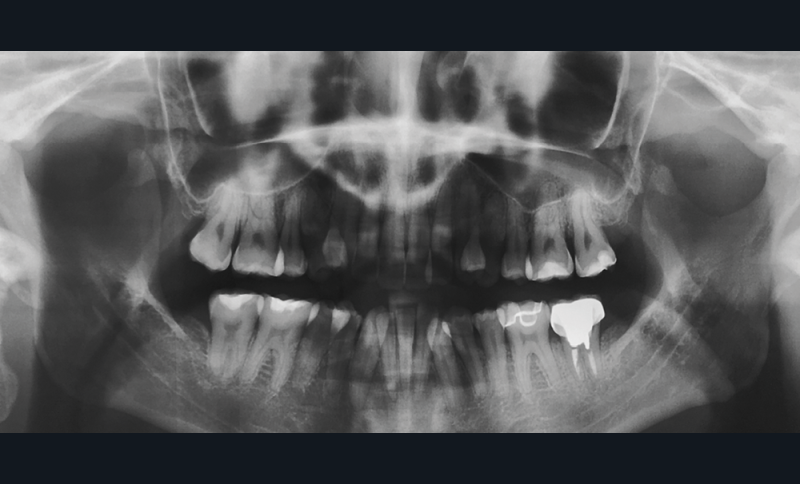

Présentation du cas (fig. 1 à 9)

La patiente présente par ailleurs une parodontite chronique modérée stabilisée (Stade 3, grade C selon la classficaiton de Chicago 2018) et bénéficie d’une maintenance trimestrielle chez son parodontiste, qui nous donne son accord pour le traitement orthodontique moyennant un suivi très régulier.

Sur le plan squelettique, on retrouve une classe III de Ballard par hypomaxillie, dans un schéma facial hyperdivergent.

Sur le plan dentaire, la patiente est en classe III droite et gauche, canine et molaire de 6 mm, avec une occlusion inversée antérieure localisée à 11, 12 et 22. Elle présente une dysharmonie dents-arcades sévère, une agénésie d’une incisive mandibulaire est à signaler, et les troisièmes molaires ont été extraites à l’âge de 21 ans.